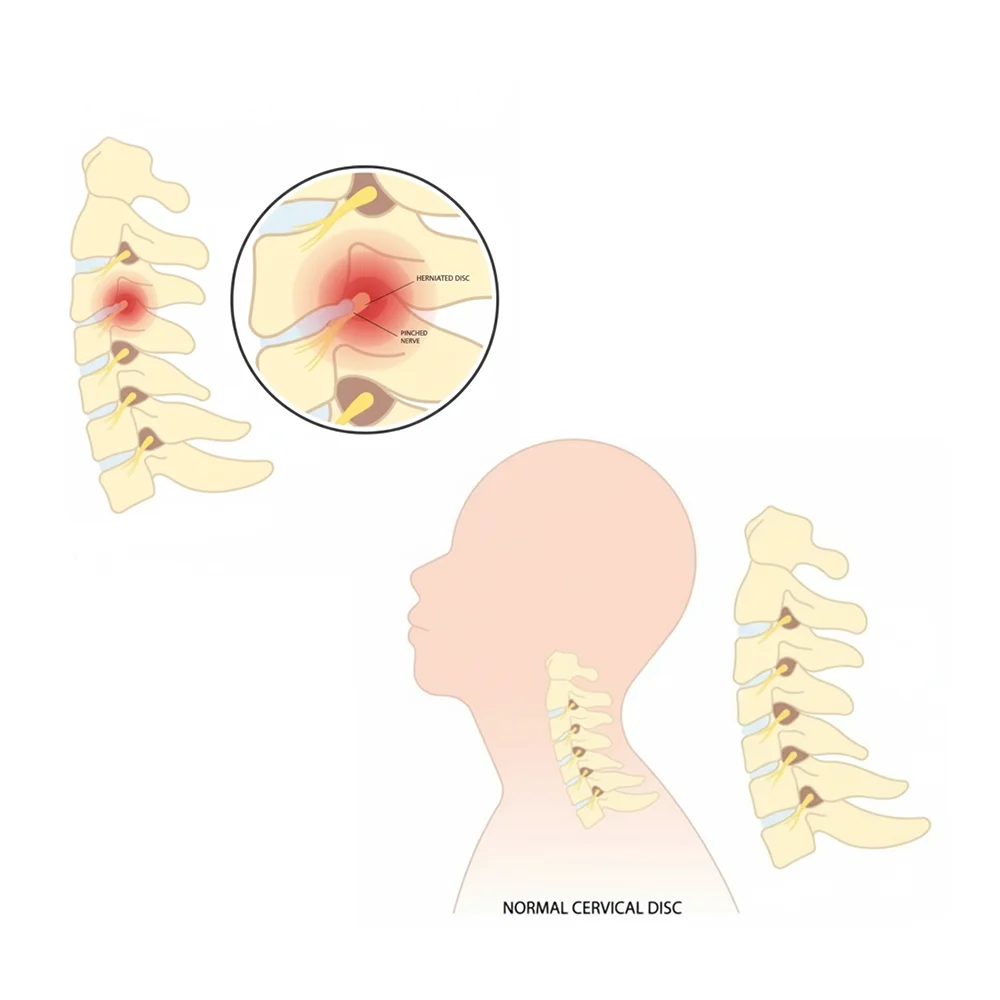

Cervical Pain

Cervical pain happens when neck nerves get pressed. It can cause stiffness, sharp pain, or numbness in the neck, shoulders, and arms. With Woonac, you can naturally reduce this pain and feel relief.